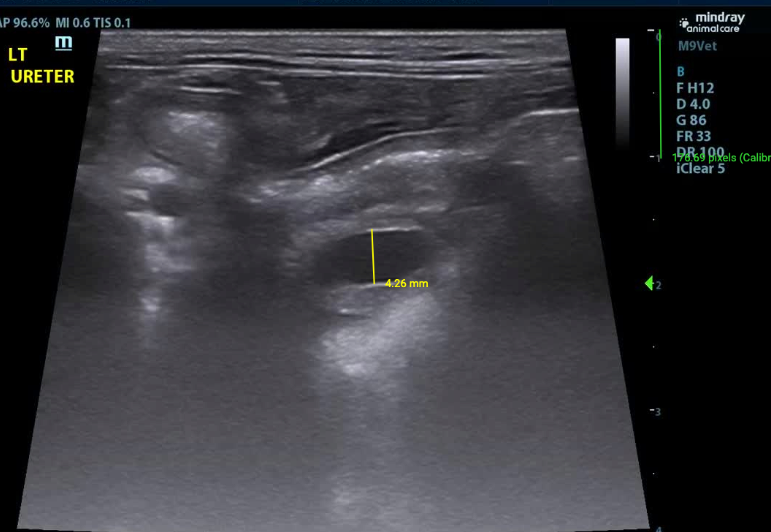

- Both ureters are mildly to moderately dilated along their length (Left - up to 4.3mm (decreased to 2.5mm at the level of the trigone); (Right up to 3.1mm - (decreased to 1.9mm at the level of the trigone)).

- The walls of the left ureter are mildly to severely and disproportionately thickened along its length (up to 5.0mm)